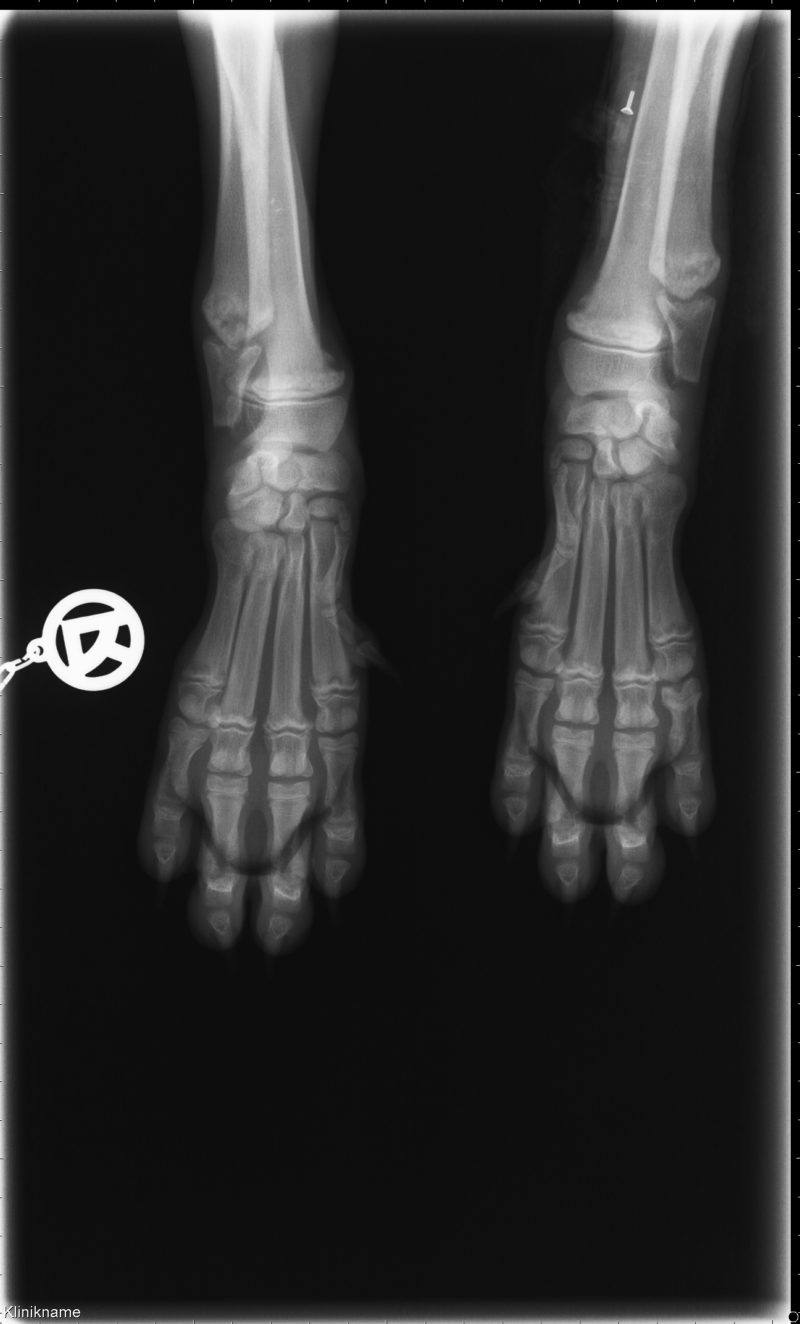

Da die Wachstumsfugen im distalen Antebrachium (Höhe der Handwurzelgelenke) schon äußerlich sichtbar stark verdickt waren, wurde die Gunst der Stunde genutzt und Röntgenaufnahmen ohne Narkose angefertigt. Das Ergebnis war für Elliot eine Überraschung, aber eigentlich eine wenn auch sehr seltene rassetypische Erkrankung des wachsenden Knochens.

Das Röntgenbild zeigt eine beidseitige HOD

Dahinter verbirgt sich die hypertrophe Osteodystrophie. Es handelt sich um eine Wachstumsstörung, die bei Welpen großwüchsiger Rassen zwischen dem 2.-7. Lebensmonat auftritt und wie bei Elliot mit Fieber, Anämie, Veränderungen im weißen Blutbild und Schmerzen in Erscheinung tritt. Die HOD wurde schon vor einigen Jahrzehnten beim Hund erstmalig beschrieben. Man vermutete immer einen Mangel in der Ernährung, insbesondere einen Vitamin C-Mangel und Fehler im Proteingehalt des Futters. Mittlerweile gibt es aber einige Berichte, Publikationen und eine Studie zum Weimaraner, die einen zeitlichen Zusammenhang mit der Impfung nahelegen. Der genaue Auslöser der Erkrankung ist aber immer noch unbekannt. Man vermutet eine genetische Veranlagung (Disposition) gegenüber modifizierten Lebendimpfstoffen, die zu einer Immunreaktion an den Knorpelzellen der Wachstumsfugen führt.